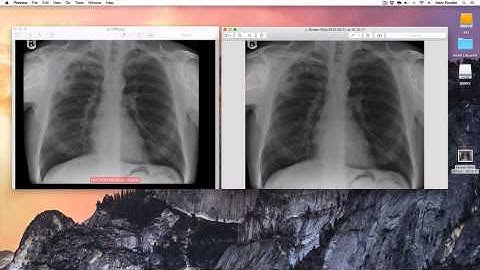

Exporter (Osirix Plugin) Demo